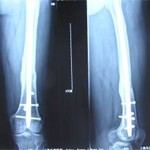

張某,男,50歲,因“左股骨骨不連”入院。植骨+PRP治療后8月完全愈合。

術(shù)前

01.jpg